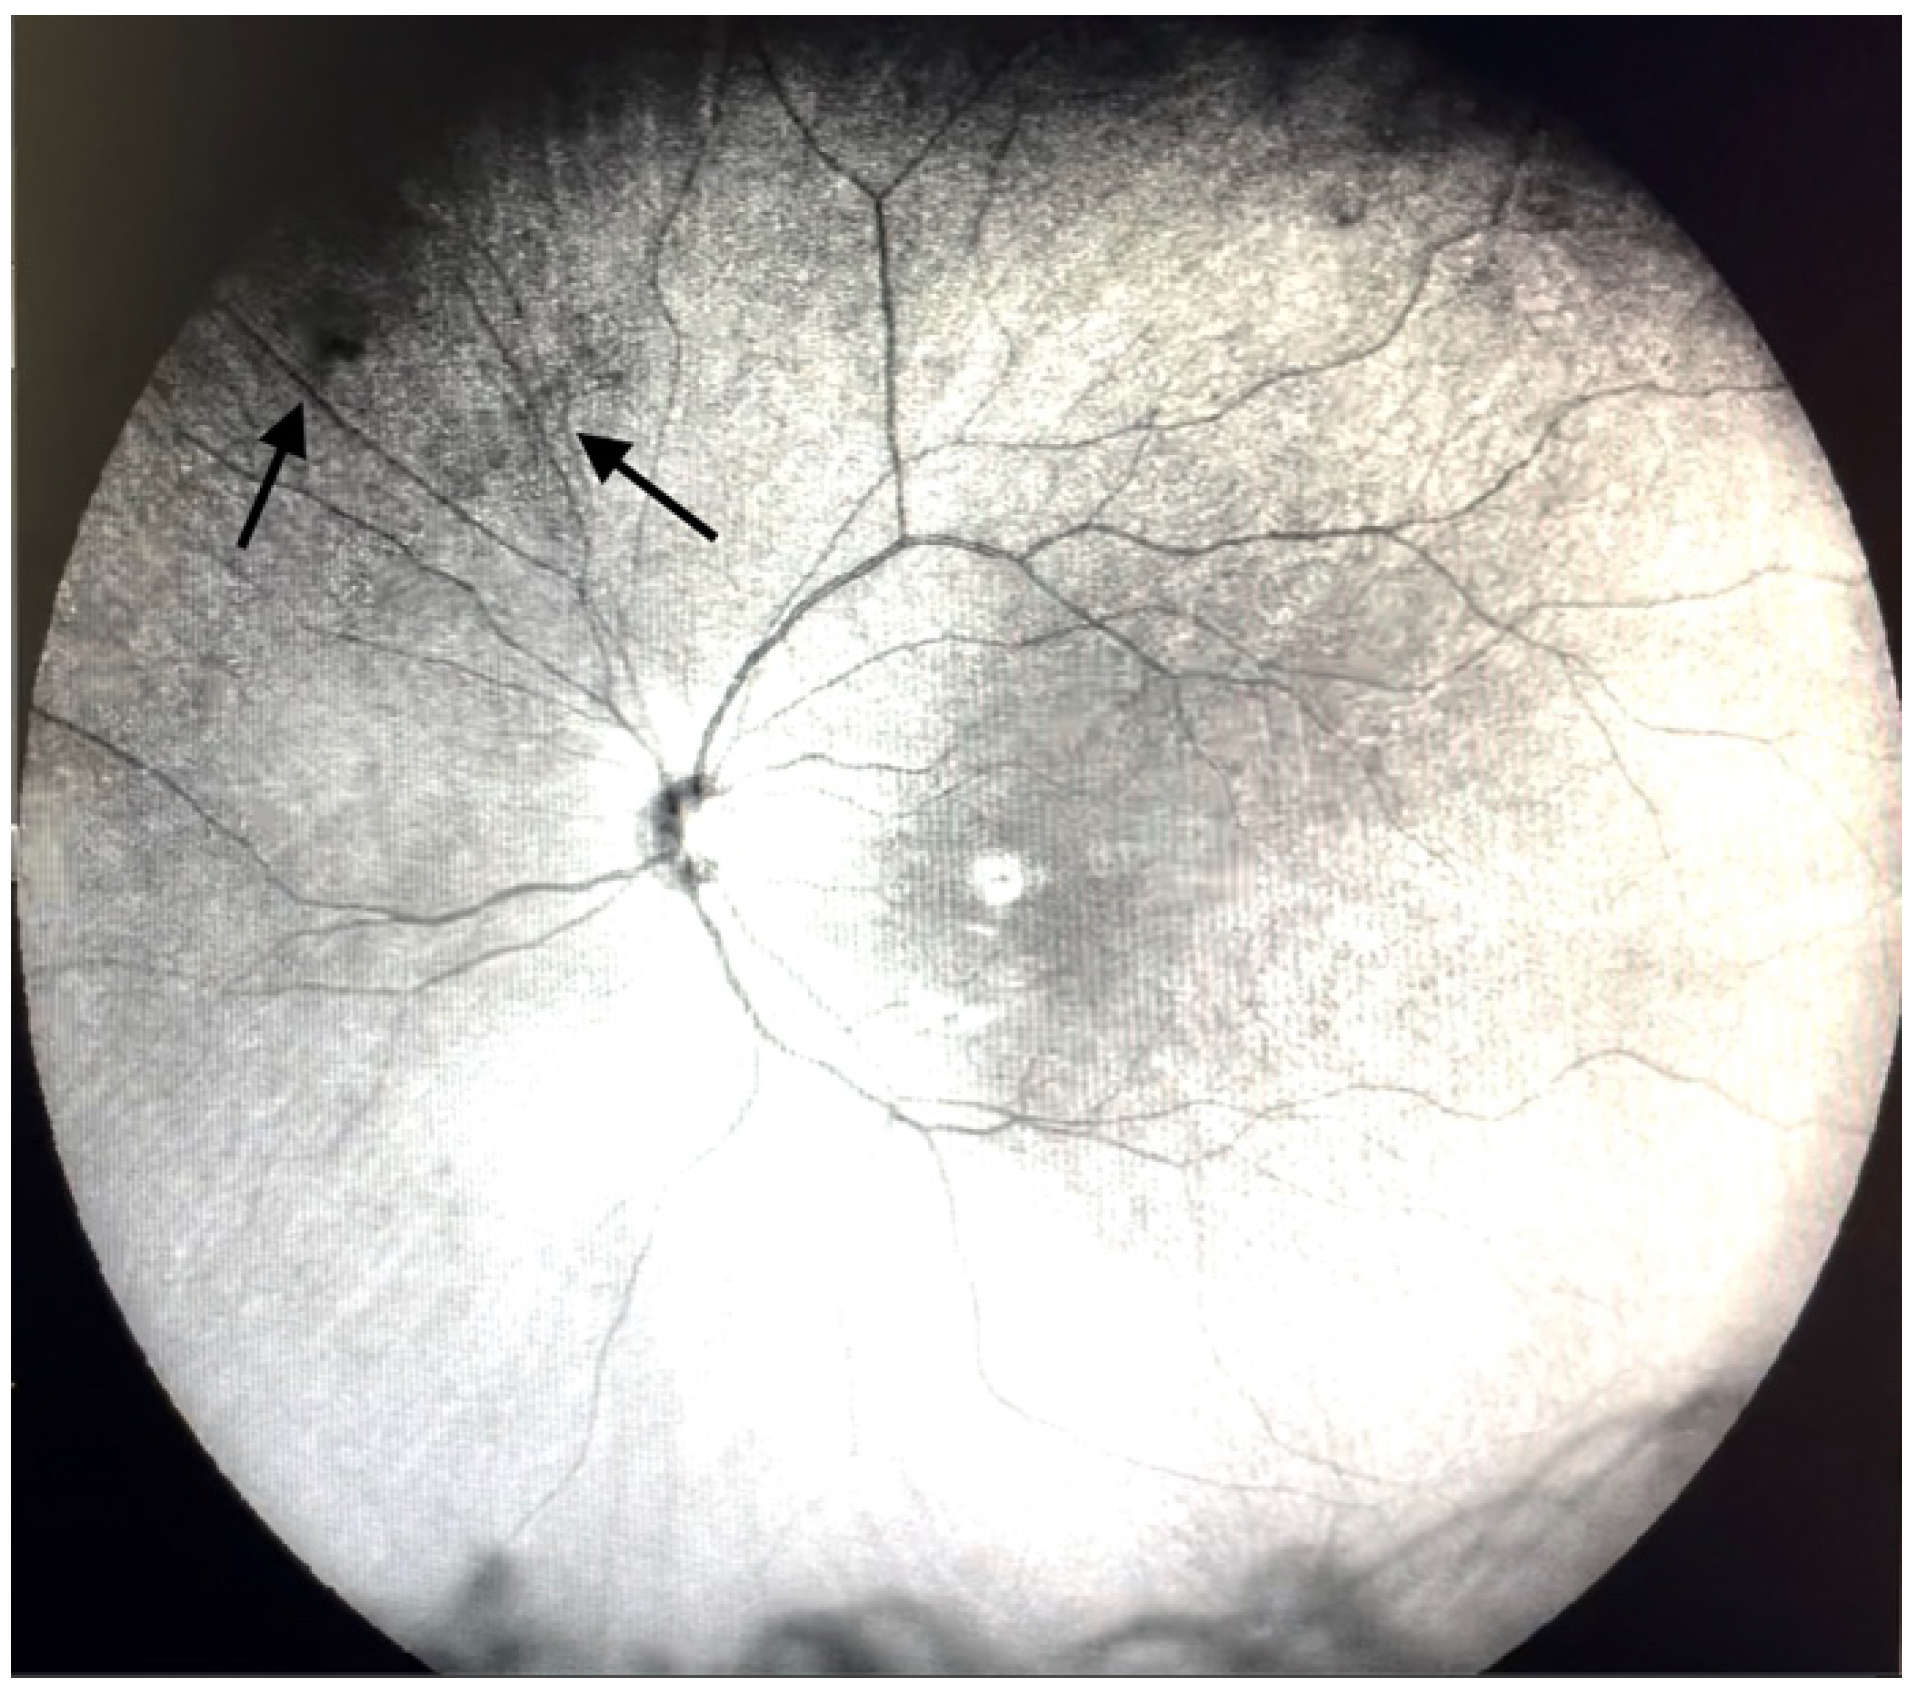

| Grade 1—Diffuse opacities that do not cross the center of the macula (Figure 2 and Video S2). |